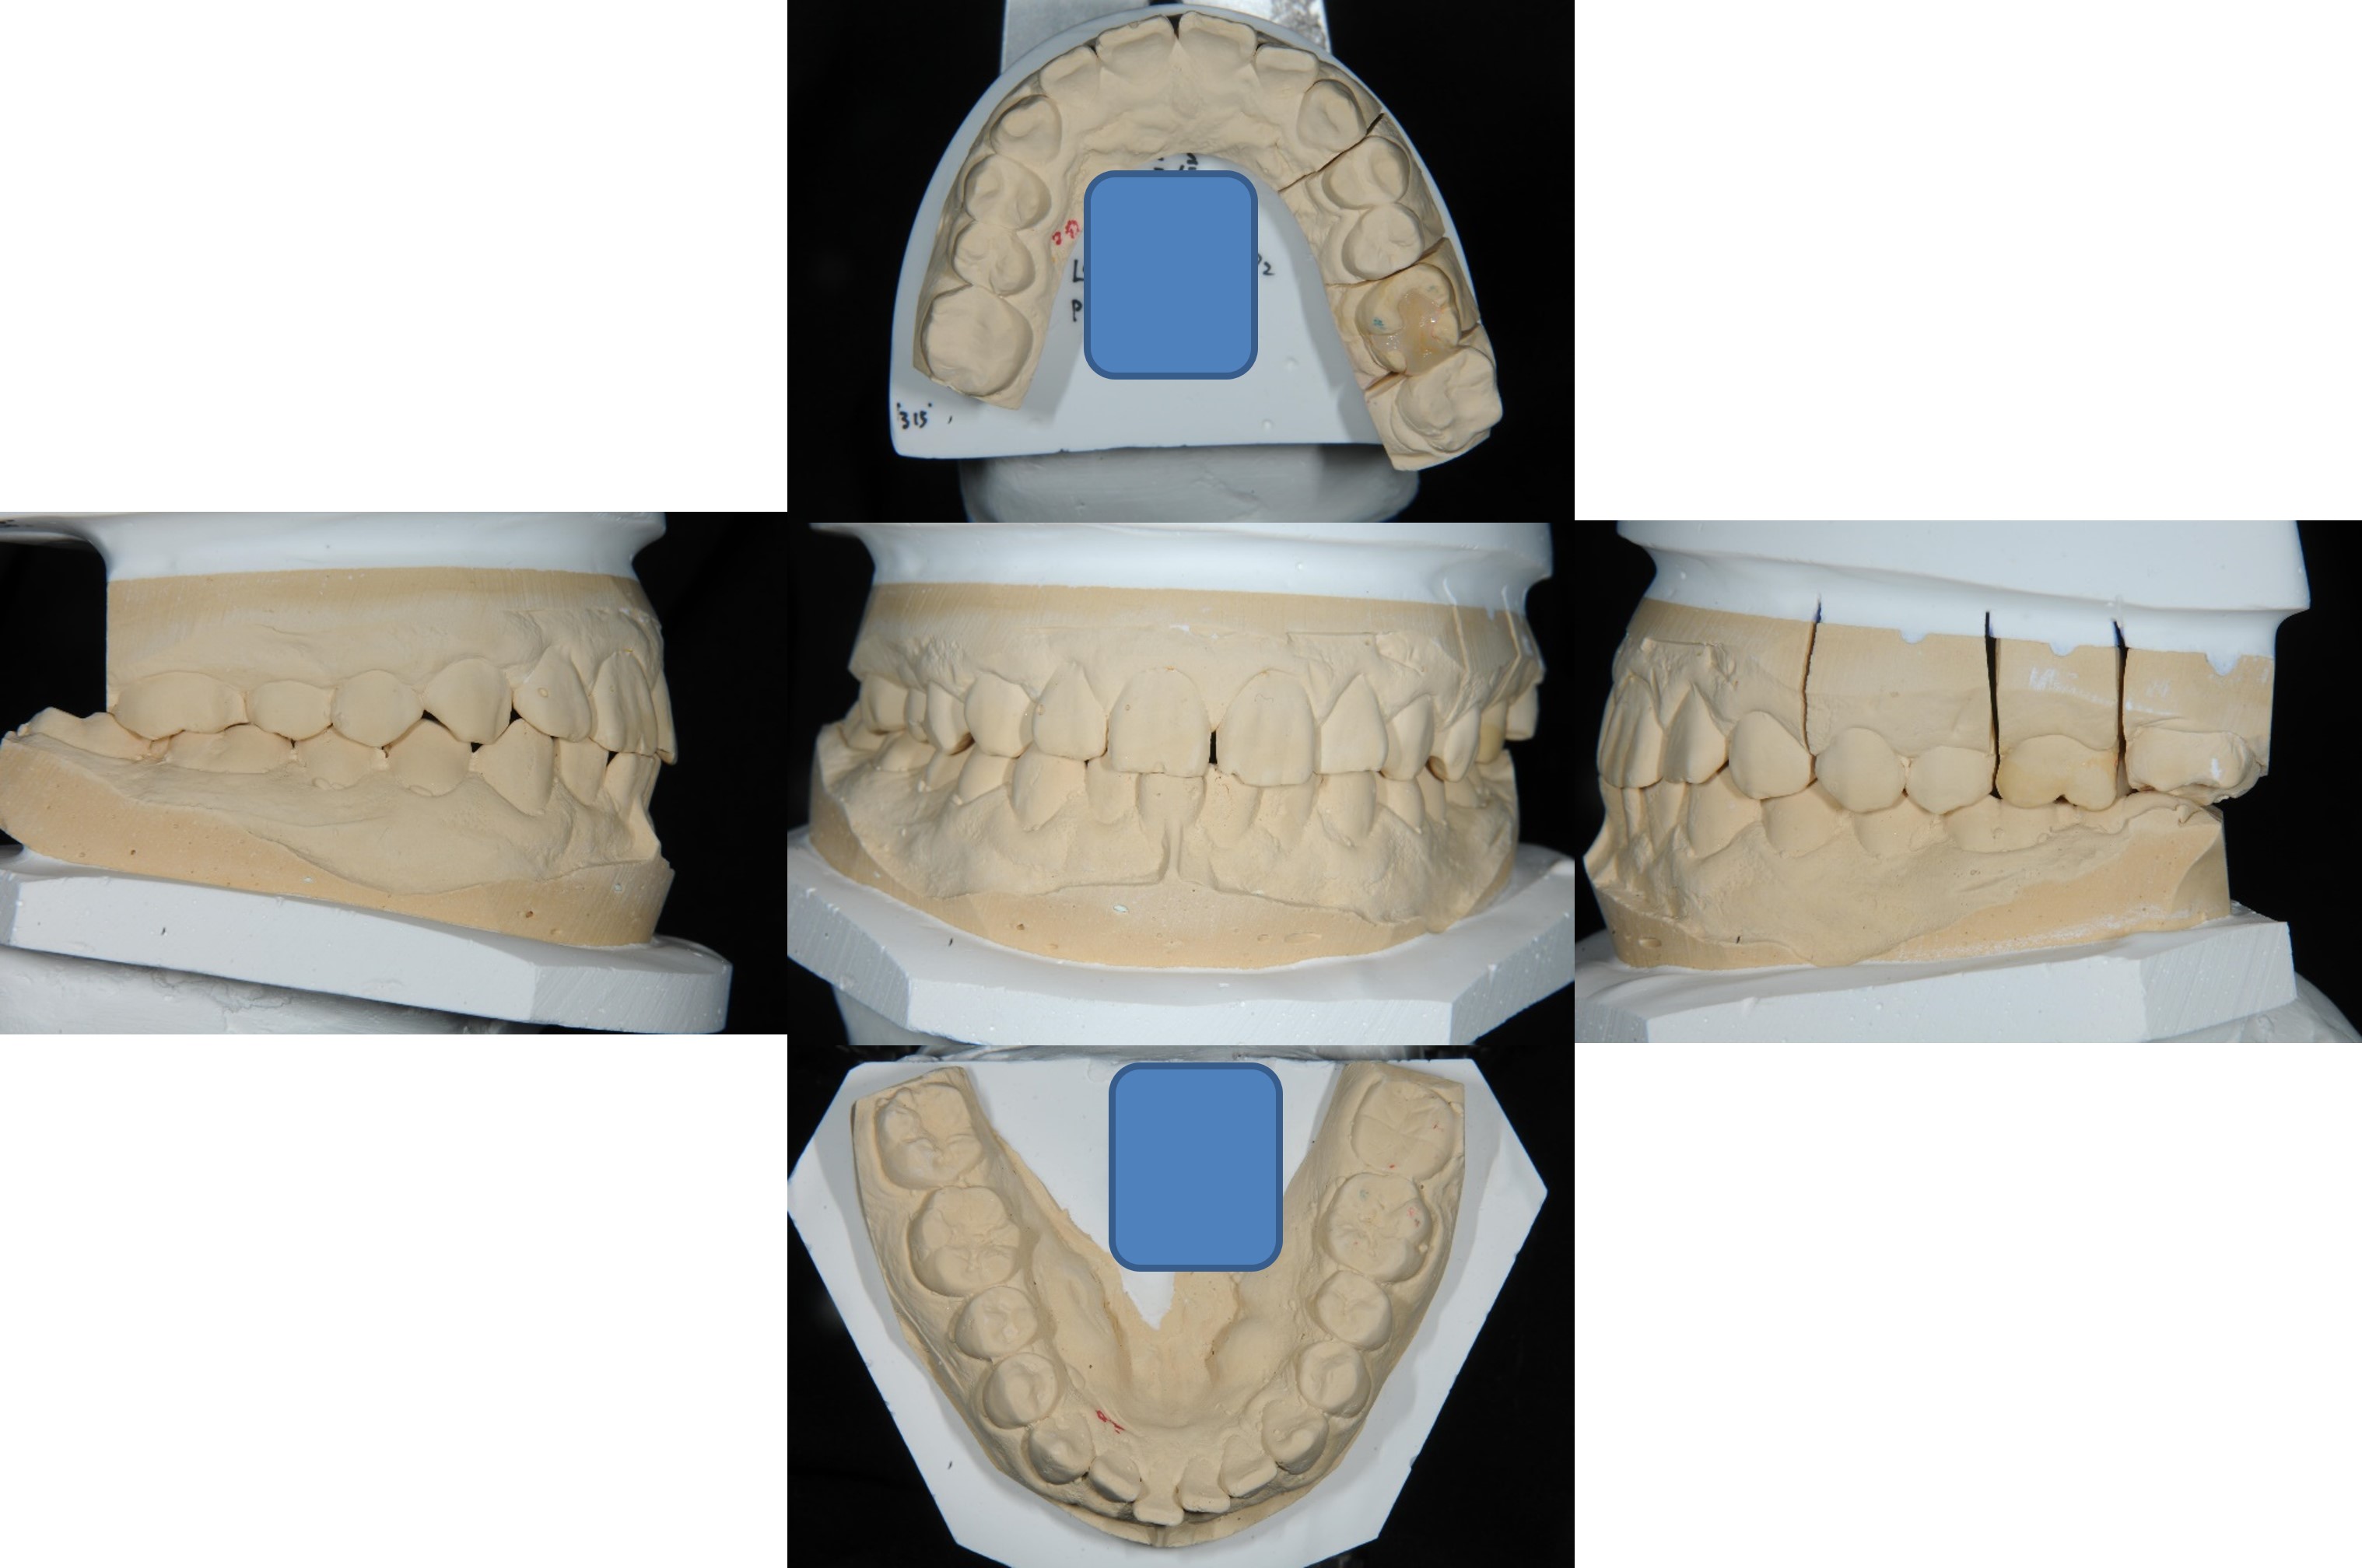

上面弓,咬合器